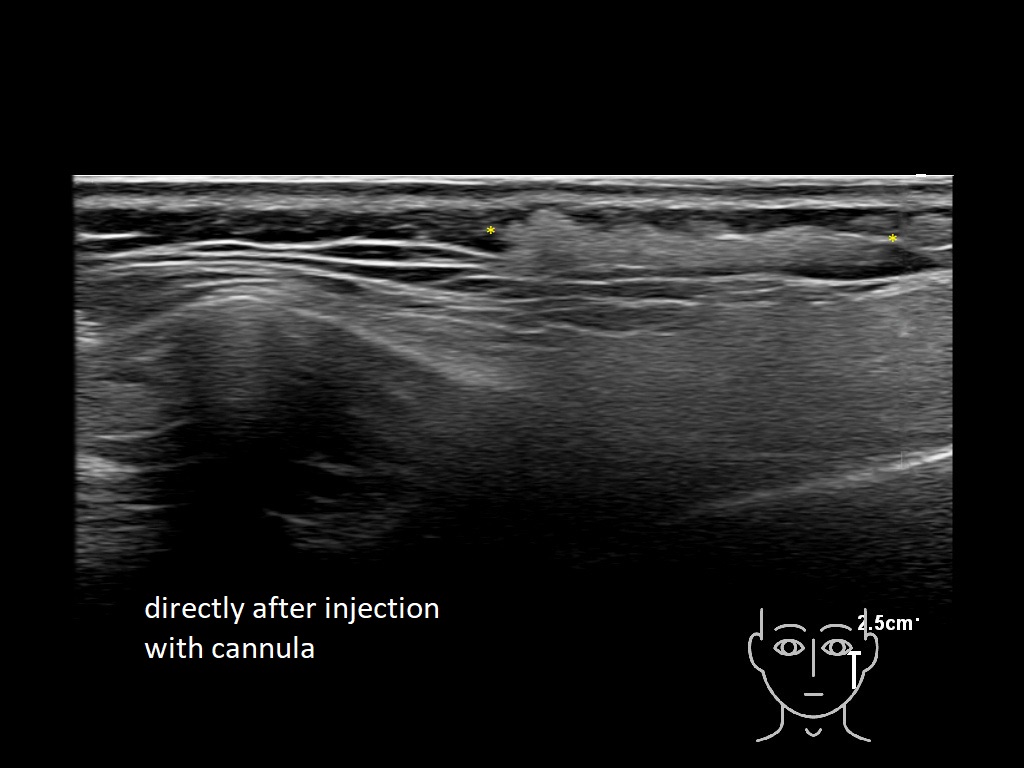

Draw in the image on the right where the fillers are located. To check if your answer is correct, please click on the secondary image.

Fillers

Draw in the second image below where the fillers are located. To check if your answer is correct, swipe the first image to the right.